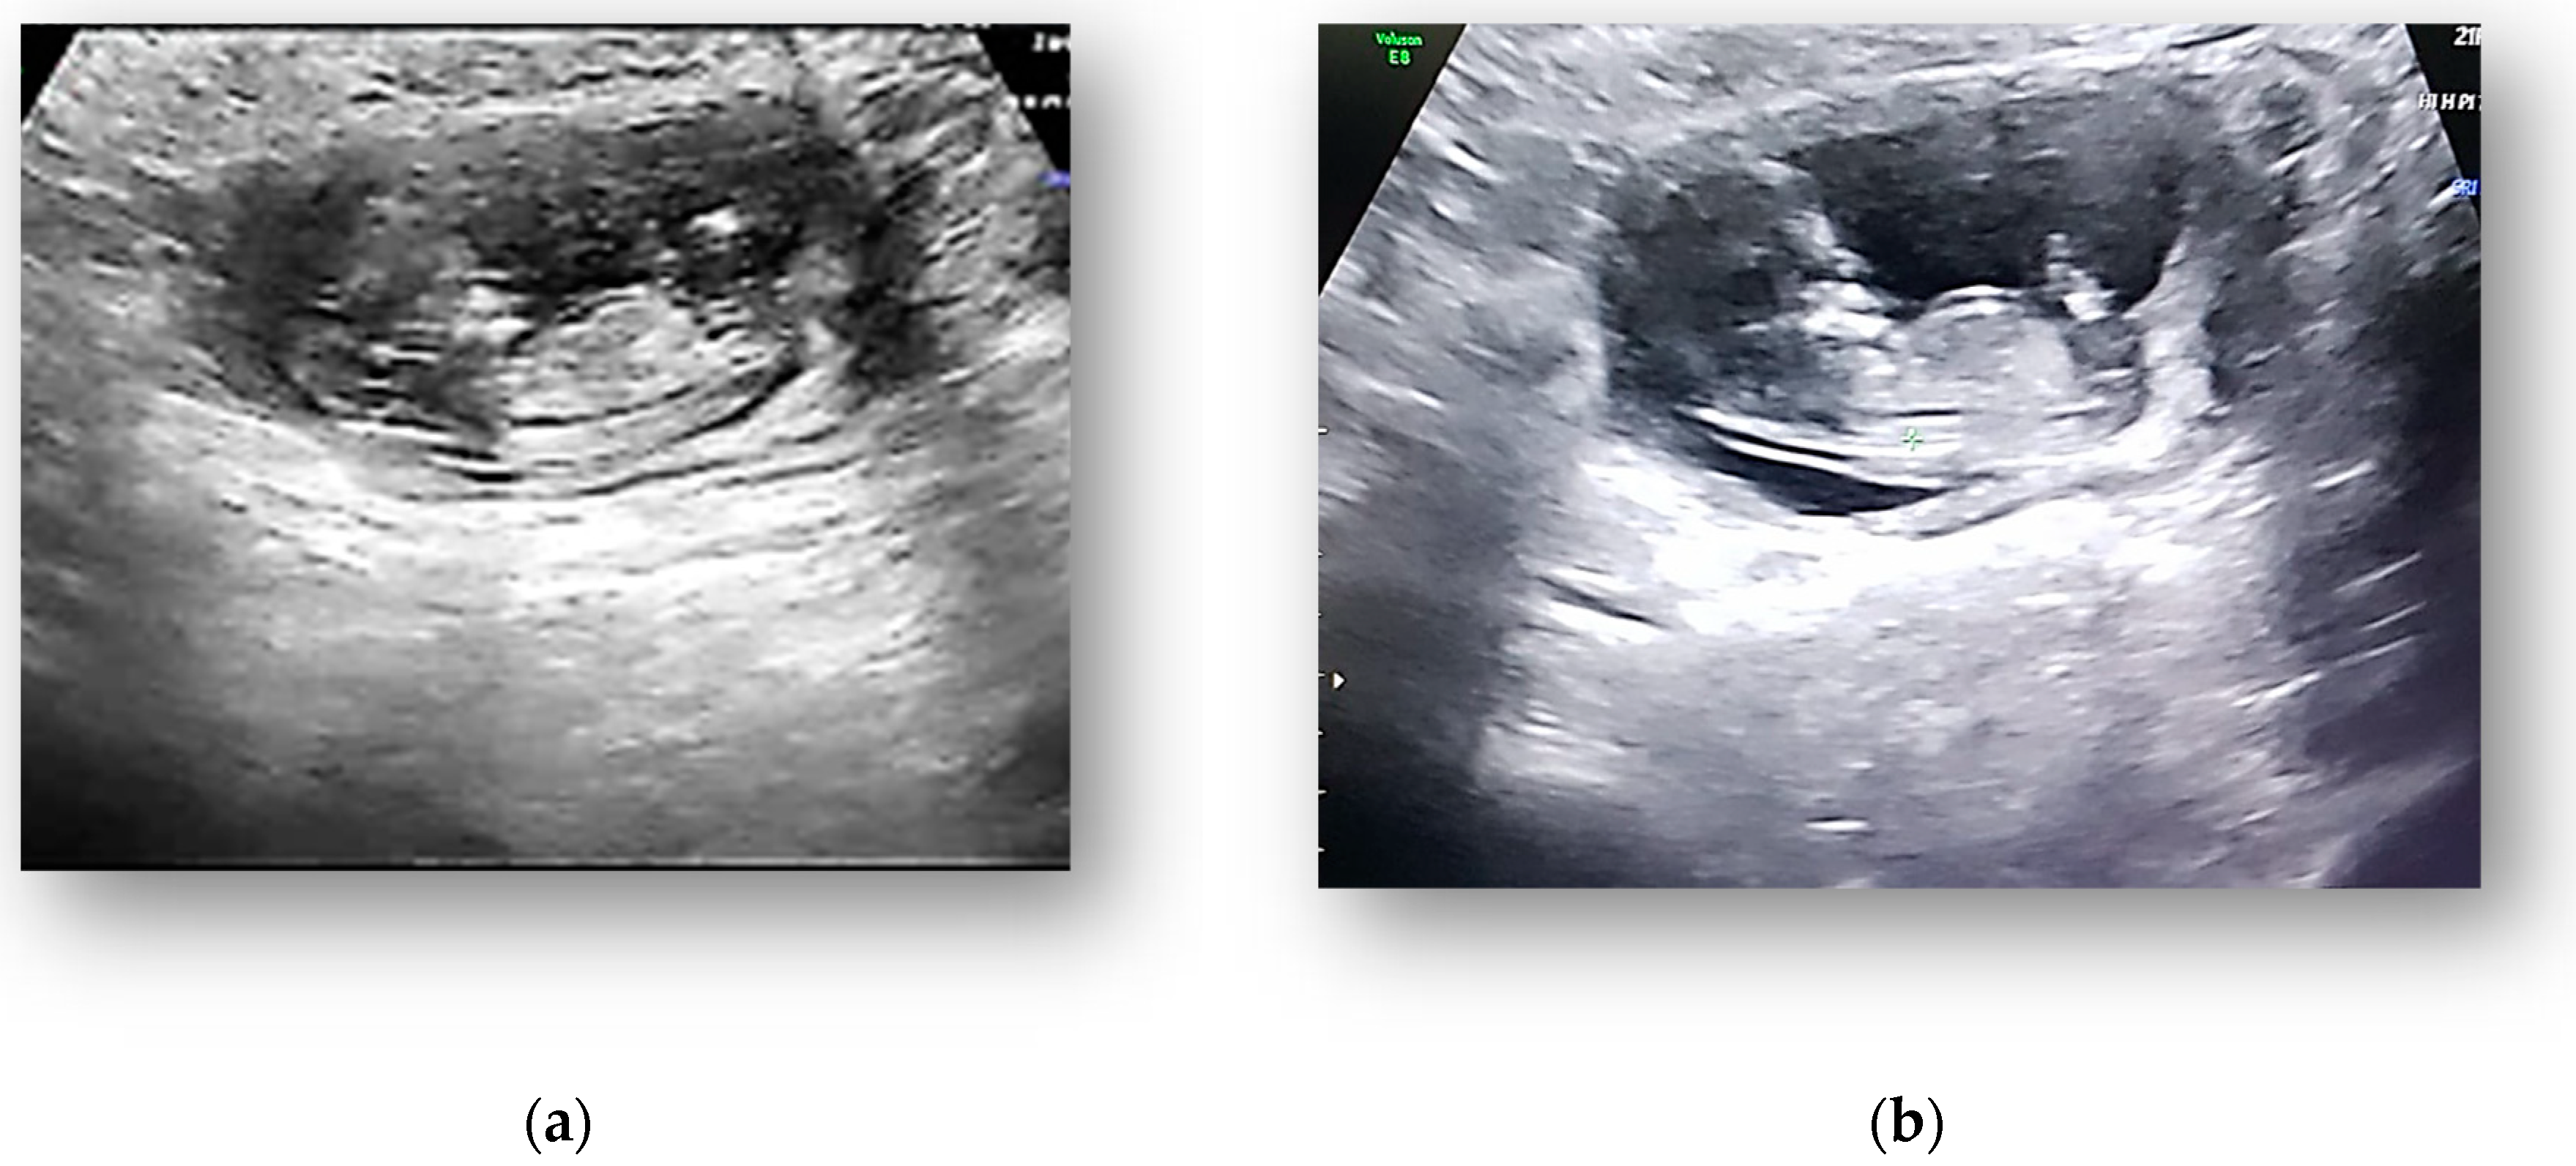

2.3. Diagnostic Assessment and Investigations